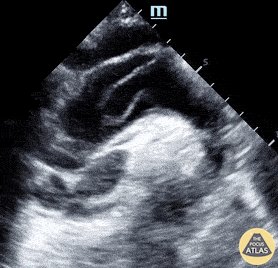

Suprasternal aortic view #POCUS #anatomy

- used in the evaluation of aortic aneurysms, dissection, c...

Suprasternal aortic view #POCUS #anatomy - used in the evaluation of aortic aneurysms, dissection, coarctation, quantifying aortic regurgitation etc. #MedEd #IMPOCUS https://t.co/K...